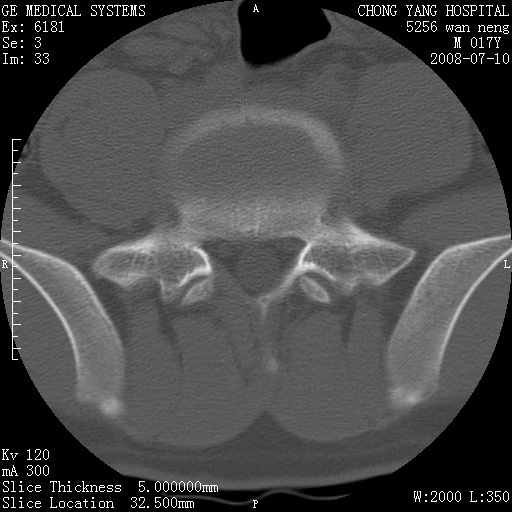

骨囊肿?

腰3、4椎弓崩裂

腰3、4椎弓不连

支持:腰3、4椎弓峡部崩裂。

腰3、4椎弓峡部不连

支持:腰3、4椎弓峡部崩解。

腰3、4,如受过外伤则为陈旧骨折,否则为骨质不连

图片漂亮,目前也只能看到腰3、4骨质不连

腰3、4椎弓峡部裂。

腰3、4椎弓峡部裂。支持

重建图像见多个椎弓峡部不连(不足为据),平扫未见异常。

支持腰3、4椎弓峡部崩裂。